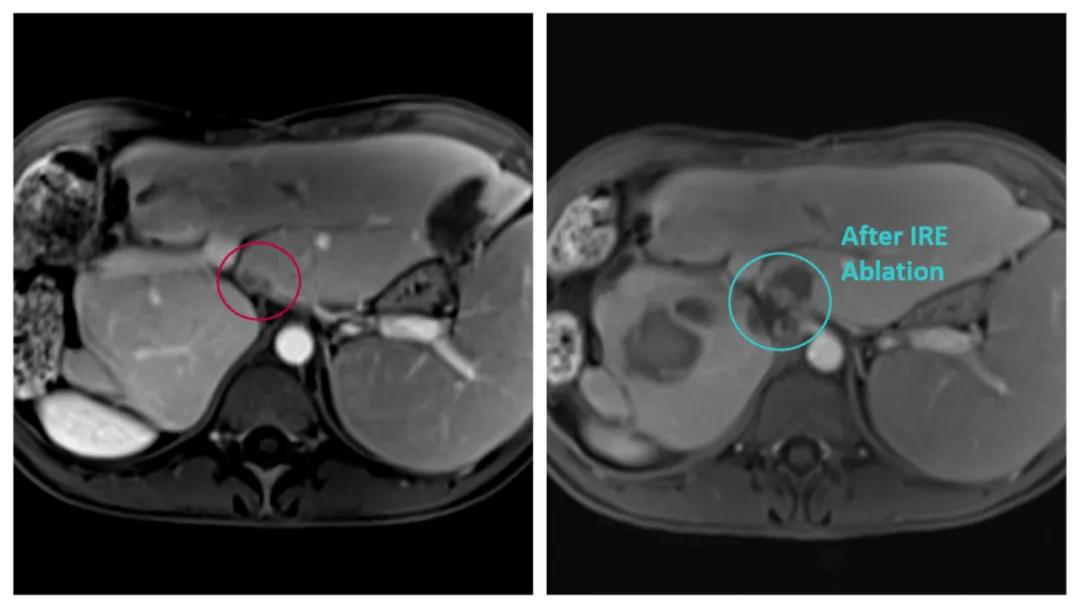

手术患者为一名33岁女性,患者既往因肝转移瘤行扩大右半肝切除术(IV-VIII),术后复发为肝脏多发转移,且转移瘤有单发病灶(1.7 x 1.6mm)靠近门静脉左支,经过多学科讨论方案:转移瘤较小,可以行介入治疗。Dophi™N3000采用不可逆电穿孔原理,在灭活肿瘤细胞的同时能够实现对脉管系统和细胞外基质的保留作用,成为该病灶的首选消融技术。本次手术在全麻状态下进行,采用心电同步模式,依次平行插入3根电极针后进行消融。

(术前术后消融区对比)